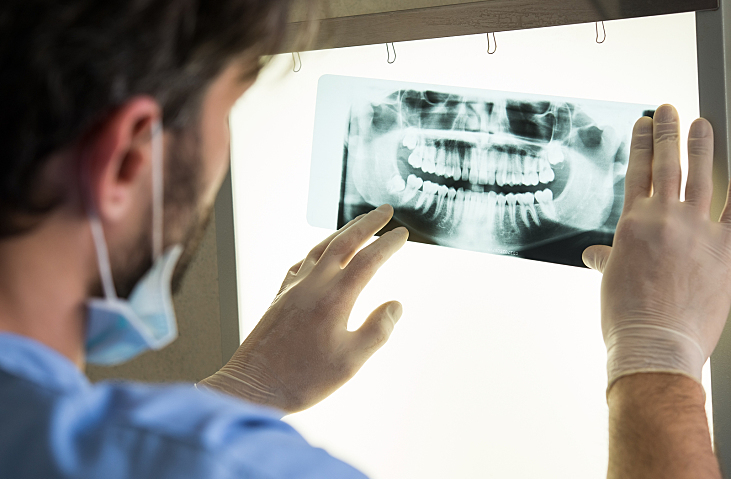

تعرف بانوراما الأسنان بأنها أشعة سينية يتم استخدامها لنأخَذ عن طريقها صورًا ملفوفةً للوجه بما في ذلك صورا للفك بالكامل، وجميع الأسنان والهياكل التي تحيط بها ، ويتمكن أطباء الأسنان استنادا إلى تلك الصور من رؤية موقع الأعصاب الأساسية ، والجيوب الأنفية، وأيضا الأسنان النامية، وغيرها من الأمراض التي تتعلق بالاسنان ، كما يمكنهم النظر إلى عظام الفم و مفصل الفك بأكمله ، وتعكِس صورة الأشعة السينية البانورامية مدى صحة الفم وسلامته ، وتقوم أشعة البانوراما بتوفير صورة ثنائية الأبعاد لنصف دائرة الفكين العلوي والسفلي، وتفيد بشكل فعال في تشخيص حالة المريض بكل أريحية وسهولة،

والأشعة السينية داخل الفم هي أكثر أنواع الأشعة السينية انتسارا ، وهناك الكثير من الأنواع من الأشعة السينية داخل الفم، حيث يمكن أن يظهر كل منها جوانب متنوعة من الأسنان حسب اختلاف زوايا تصوير الأسنان. - اشعة بانوراما للاسنان : تقوم اشعة بانوراما للاسنان بإظهار منطقة الفم بالكامل، وهي تتضمن جميع زوايا تصوير الأسنان، في كل من الفكين العلوي والسفلي في صورة أشعة سينية واحدة فقط .

ويتم استخدام اشعة بانوراما الاسنان لفحص الأسنان بالكامل والفك أيضاً، لاكتشاف أي اختلالات بالفك والأسنان، لأنها تعطي صورة كاملة وواضحة للفك والأسنان معاً ، كما يمكنها رؤية الأسنان المتأثرة وساهم فب الكشف عن الأورام.

توفر الأشعة البانورامية للاسنان للطبيب رؤية ثنائية الأبعاد من الأذن إلى الأذن أي للفكين العلوي والسفلي، وتتكون المعدات الضرورية للتصوير من ذراع دوار يحمل مولد الأشعة السينية، ومرفق بفيلم مرفق متحرك لتحميل الصور، ويُطلّب من المريض وضع رأسه بين هذين الجهازين، وخلال الإجراء يتحرك مولد الأشعة السينية حول الرأس ويلتقط الصور بشكل متعامد قدر المستطاع ، وتحدد وضعية كلًا من الرأس والجسم مدى حدة ووضوح وفائدة الأشعة السينية لطبيب الأسنان، ويتم تكبير الصور بنسبة يمكن أن تصل إلى 25% لضمان تسجيل أدق التفاصيل .